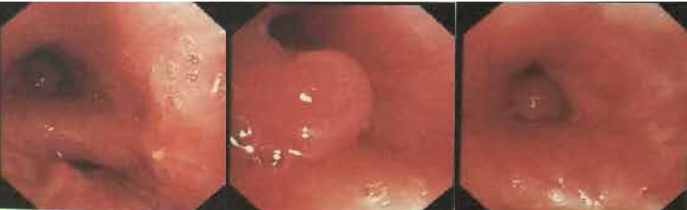

支气管镜检查可左上叶开口位置有一光滑的小结节。

图片